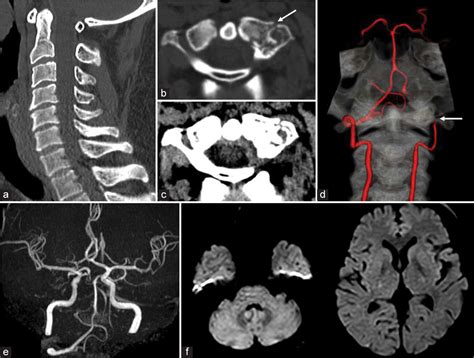

• CT Angiography (CTA): This provides a detailed 3D view of the blood vessels in the neck and brain, identifying blockages quickly.

• Magnetic Resonance Angiography (MRA): Useful for visualizing blood flow without the use of ionizing radiation.

• Digital Subtraction Angiography (DSA): Considered the "gold standard," this invasive procedure involves injecting contrast dye to map the arteries with high resolution.

• Carotid and Vertebral Ultrasound: A non-invasive method often used for initial screenings to check for plaque buildup or flow velocity changes.